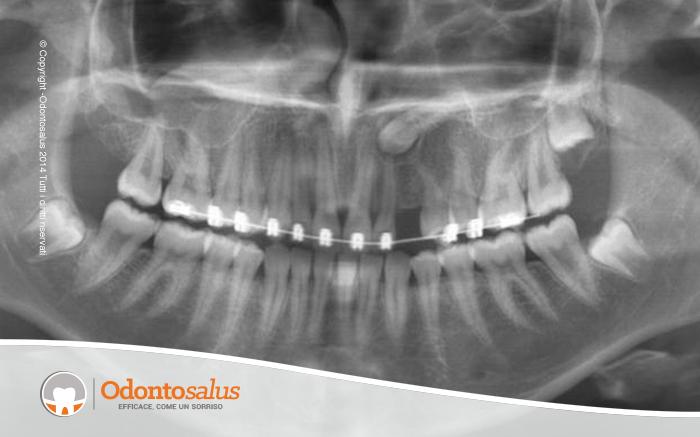

DESCRIZIONE DEL CASO Paziente con inclusione del canino (elemento 23), situato in posizione vestibolare. Come è stato possibile verificare dalle Tac eseguite, data la posizione dell’elemento, l’accesso per l’aggancio ha richiesto l’apertura di un lembo vestibolare. Inciso il lembo e scoperto il dente, si è proceduto con l’applicazione di un bracket con catenella per la trazione del canino incluso.